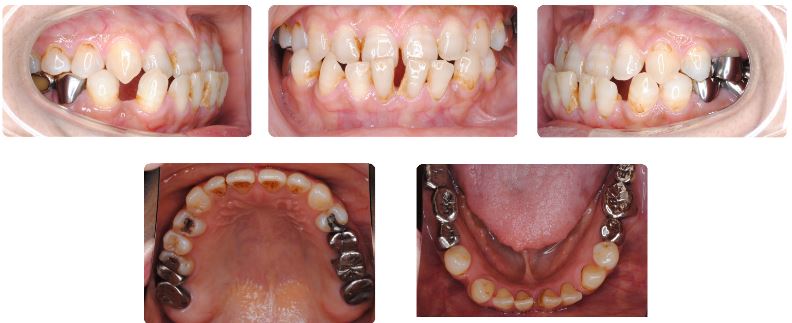

主訴:前歯の見た目が気になる

初診時年齢:57歳

性別:女性

診断名:舌癖と舌小帯強直を伴う反対咬合

抜歯/非抜歯:非抜歯

装置名:マルチブラケット装置

前歯の噛み合わせを長年気にしていたとのことで来院です。

50代後半のご年齢ですが、歯周組織の状態が非常に良好ですのですぐに治療開始いたしました。